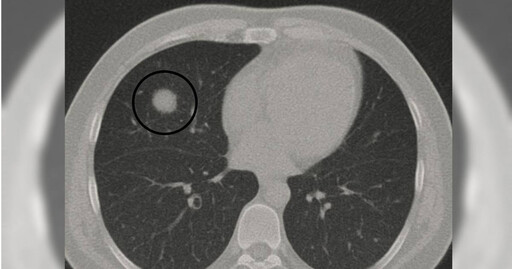

營養功能學名醫劉博仁今(2日)在臉書粉專發文分享2個真實病例,提醒大眾面對肺部結節時應保持警覺,但也不要過度恐慌。首先,第一位病患在醫院進行低劑量電腦斷層(LDCT)檢查時,發現肺部有一個1.2公分的不規則結節。

對此,劉博仁醫師強烈建議立即開刀,但病患猶豫不決,最後選擇先以功能醫學調理並密切追蹤。4個月後再檢查,結節縮小到僅剩0.3公分,最終確認只是因感染造成的假性結節,幸運地避免了不必要的肺部手術。

另一位病患則是女性,右上肺發現0.9公分的毛玻璃樣結節。起初半年間形狀沒有變化,但隨後逐漸長大。劉博仁醫師強烈建議手術,病理結果證實為第一期肺腺癌。由於及早發現與處理,成功切除且沒有擴散,病患因此保住了健康。

劉博仁醫師強調,LDCT是目前最有效的早期肺癌篩檢工具,能夠發現小於1公分的結節,遠優於傳統胸部X光。醫師會根據國際Fleischner指南與臨床經驗來判斷是否需要手術,若結節大於8毫米且形狀不規則、毛玻璃樣結節持續增大、出現明顯實性成分,或病患屬於高危險族群,就應積極處理,以免錯過治療時機。